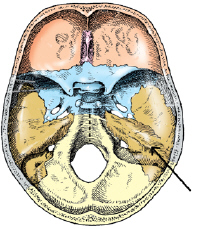

the posterior half of the base of the skull is formed by which bone

occipital

the tickest and densest portion of bone in the cranium is the

petrous portion of the temporal bone

the superior aspect of the sphenoid bone contains a deep depression that contains the

pituitary gland

the large aperture in the occipital bone through which the medulla oblongata and spinal cord exits the

foramen magnum

the base of the anterior portion of the occipital bone contains two large opening that allow blood vessels and nerves to pass through. these two openings are called the

jugular foramina